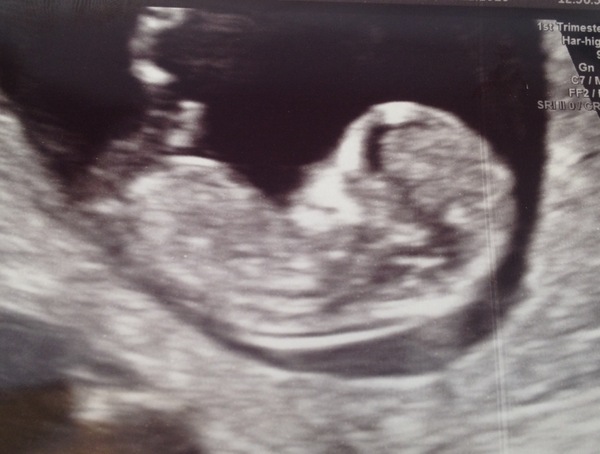

We had our scan today :) all looks good, very wriggly baby! Looks so much bigger than I thought it would be! Dates were exact so I can stay on the June board!! EDD 1/6/17!

Ah that's a lovely clear scan! Congrats! Cat x

Lovely scan walker xx

Fab scan walker!! So cute

Lovely pic of baby there! It all starts to feel real once you see the little bean.

walkerbean what a beautiful scan photo!!!! Our babies are proper 'babies' eh?! Cysts on ovaries are very common, yes, so nothing to worry there as moonlight said. Most ovaries create them all the time strange things